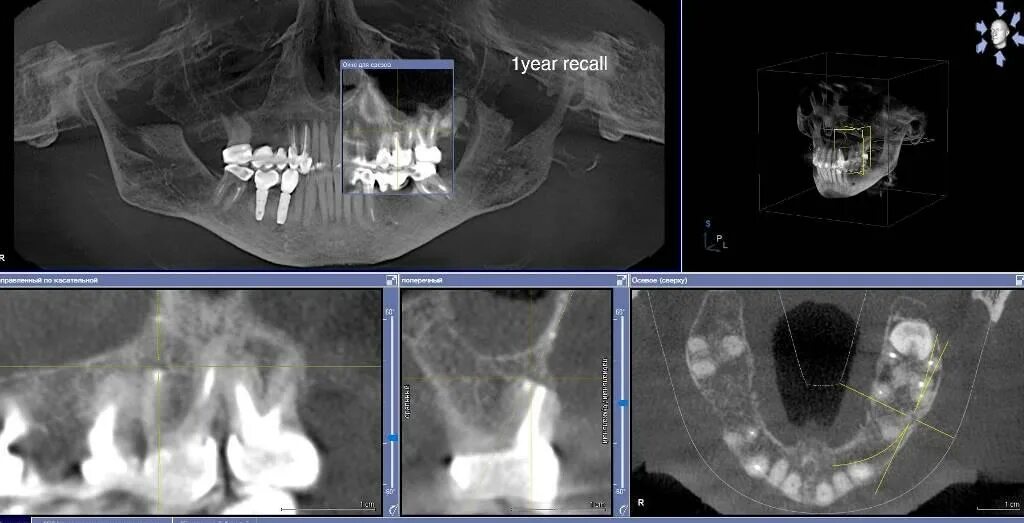

Ретроградное пломбирование корневых